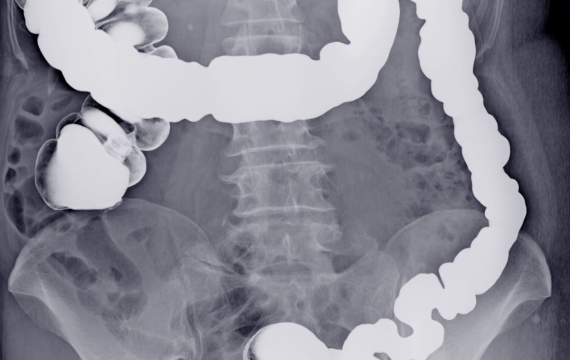

• Colonoscopia: se utiliza una cámara para visualizar el colon y el recto.

Image

escaner-en-valencia